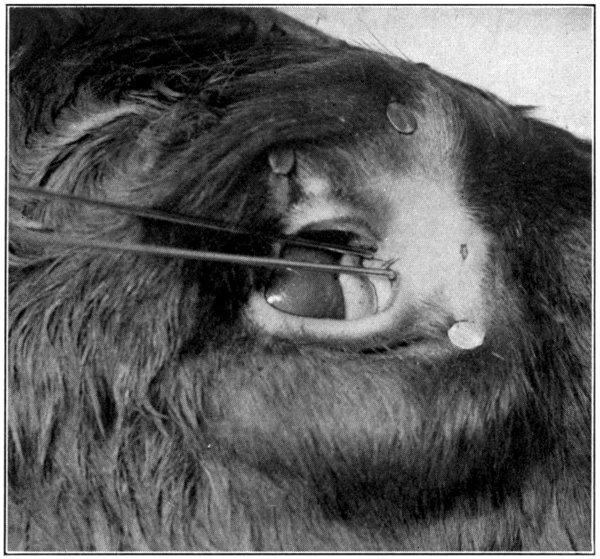

Fig. 45—Showing only a part of a calf’s head and the knitting-needles inserted in the puncta. (Page 94.)

Fig. 46.

Be supplied with two knitting-needles. Take one, lubricate its full length with a little vaseline, lard, oil, or any other lubricant. Insert the needle into the punctum of the[93] lower lid, and push it downward and forward, aiming to come out in the nose a short distance from its end. At first it may be a little difficult to get the needle started; if so, just wiggle the needle, pushing it at the same time as directed, until the nasal duct is found. Do not remove the needle. To insert the other[94] needle into the punctum of the upper lid is rather difficult; for that reason the punctum of the lower lid was chosen, first. Grease the needle, as was done to the first one, and, with a little patience and careful manipulation, the canal opening and its course will soon be found. The needle may then be pushed through until it meets the first one. (Fig. 45.)[95] From the puncta lacrimalia to the place of meeting of the two needles, marks the course of the two canaliculi and their junction before they merge and form the nasal duct. Leave the needles where they are, and begin cutting away the skin. The needles will then mark the course of each canal and the duct very plainly. With the small scissors the canals and the duct may be loosened from the surrounding tissues. Or, the scalpel may be used to lay open the canals, cutting along over the top of the needles. (Fig. 46.)